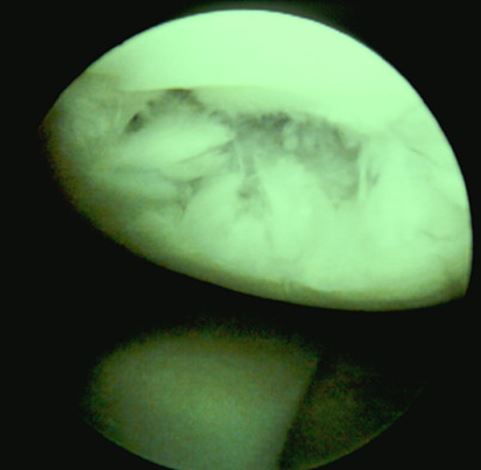

骨性关节炎镜下表现

I度:关节内软骨软化

II度:关节内软骨龟裂

III度:关节内软骨溃疡,纤维化

IV度:关节内软骨剥脱,软骨下骨质外露,象牙质变